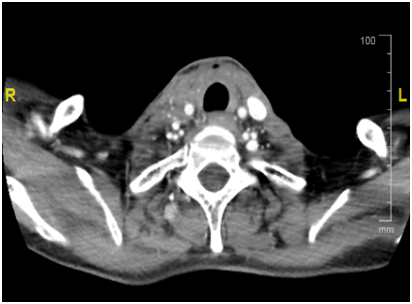

Our patient is a 55yrs. old female with long standing history of Goitre. She underwent total thyroidectomy after confirming Papillary Thyroid cancer on FNA at presentation with slowly progressing neck mass over a course of 1yr. Initial TNM stage showed a T3 N1 M0 Papillary thyroid tumour with extra capsular extension. She proceeded to have radio iodine ablation in May 2016 with 5000Mbq which showed uptake in thyroid bed and Rt neck nodes at level 2. She was then maintained on TSH suppressive dose of thyroxine. Unfortunately, she suffered a relapse in the neck with neck nodes 3 months later i.e. in august 2016 and proceeded to have neck clearance. Again nodes in the RT neck were noted along with extra capsular extension. Pathology, however, showed anaplastic thyroid cancer. Within 6 weeks from her second surgery she came back with rapidly progressing bilateral lower neck nodes. She had a CT which confirmed the recurrence with no distal metastasis. Her recurrence, now second after initial surgery, was deemed inoperable due to the tumour being wrapped around the carotid artery. She proceeded with External Beam Radiotherapy for local control. She progressed on radiotherapy within 2weeks of the start of treatment. This was confirmed on repeat CT scan. No distal metastasis was detectable. Unsurprisingly patient’s thyroglobulin levels were never very high (max level of 20.6). Subsequent levels were within normal limits with no detectable Anti Thyroglobulin Antibody. At this point patient was started on 24mg of Lenvatinib. On her next follow up after 2weeks patient had a complete clinical resolution of her neck nodes and a subcutaneous suprasternal mass as seen previously showed considerable shrinkage. Patient remained troubled with grade 2 fatigue and anorexia but nothing else. At her next appointmentafter2 weeks she had complete disappearance of her disease so much so that a crater was left in suprasternal area i.e. site of her previous subcutaneous tumour extension. Due to persistent fatigue and anorexia dose of Lenvatinib was reduced to 14mg which she is tolerating well. She had a CT at 6weeks which confirmed complete resolution of her disease and no metastasis. She has recently undergone debridement of the lower anterior neck wound and no disease has been detected on biopsy. She awaits her next staging CT in near future (Figure 1).